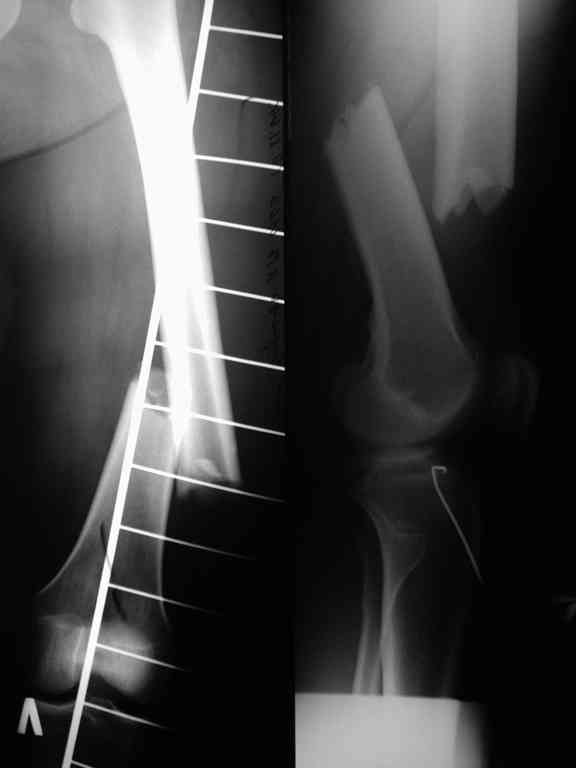

В приложении рентгенограмма бедра за авгутст 2005 с согнутым гвоздем и первичные.

Отсутствие сращения косвенно говорит об этом. Хотя, судя по снимкам со стержнем, вероятны и другие проблемы. Раз есть диастаз - надо динамизировать стержень практически сразу, недели в 2-4 после остеосинтеза, а раз уж сращения в динамике не выявляется, зачем было с динамизацией ждать больше 2 мес.?

Чтобы рассверливание обусловило несращение, надо сверлить невесть чем и как, чтобы вызвать термический некроз на всю толщину кости. Так что в рассверливании искать источник бед я бы не стал. Проблемы обычно бывают от скелетирования кости. Плюс оставлен диастаз (мальротация?). Да и функция/нагрузка конечности были долго ограничены, что тоже неполезно.

Обычно достаточно закрыто перештифтовать стержнем большего диаметра, рассверлив канал. Зачем перешли на пластину?